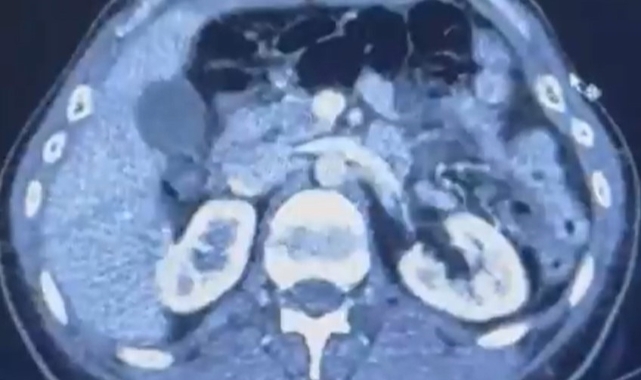

Edinilen bilgiye göre Narkotik Suçlarla Mücadele Şube Müdürlüğü ekiplerince uluslararası uyuşturucu madde ticareti yapan kurye şahıslara yönelik gerçekleştirilen çalışmalarda, İran’dan Türkiye'ye uyuşturucu madde getirdiği tespit edilen şüpheli şahısların yakalanması amacıyla operasyon düzenlendi. Düzenlenen operasyonda; S.C., R.B.C. ve G.M. yakalandı. S.C. ve R.B.C.'nin Kayseri Şehir Hastanesi'nde yapılan iç beden muayenelerinde, mide kısımlarında bulunduğu tespit edilen 50 adet kapsül şeklinde toplam 554 gram uyuşturucu madde ele geçirildi. Şüpheliler gözaltına alınarak haklarında 'Uyuşturucu Madde Ticareti Yapmak' işlem başlatıldı.